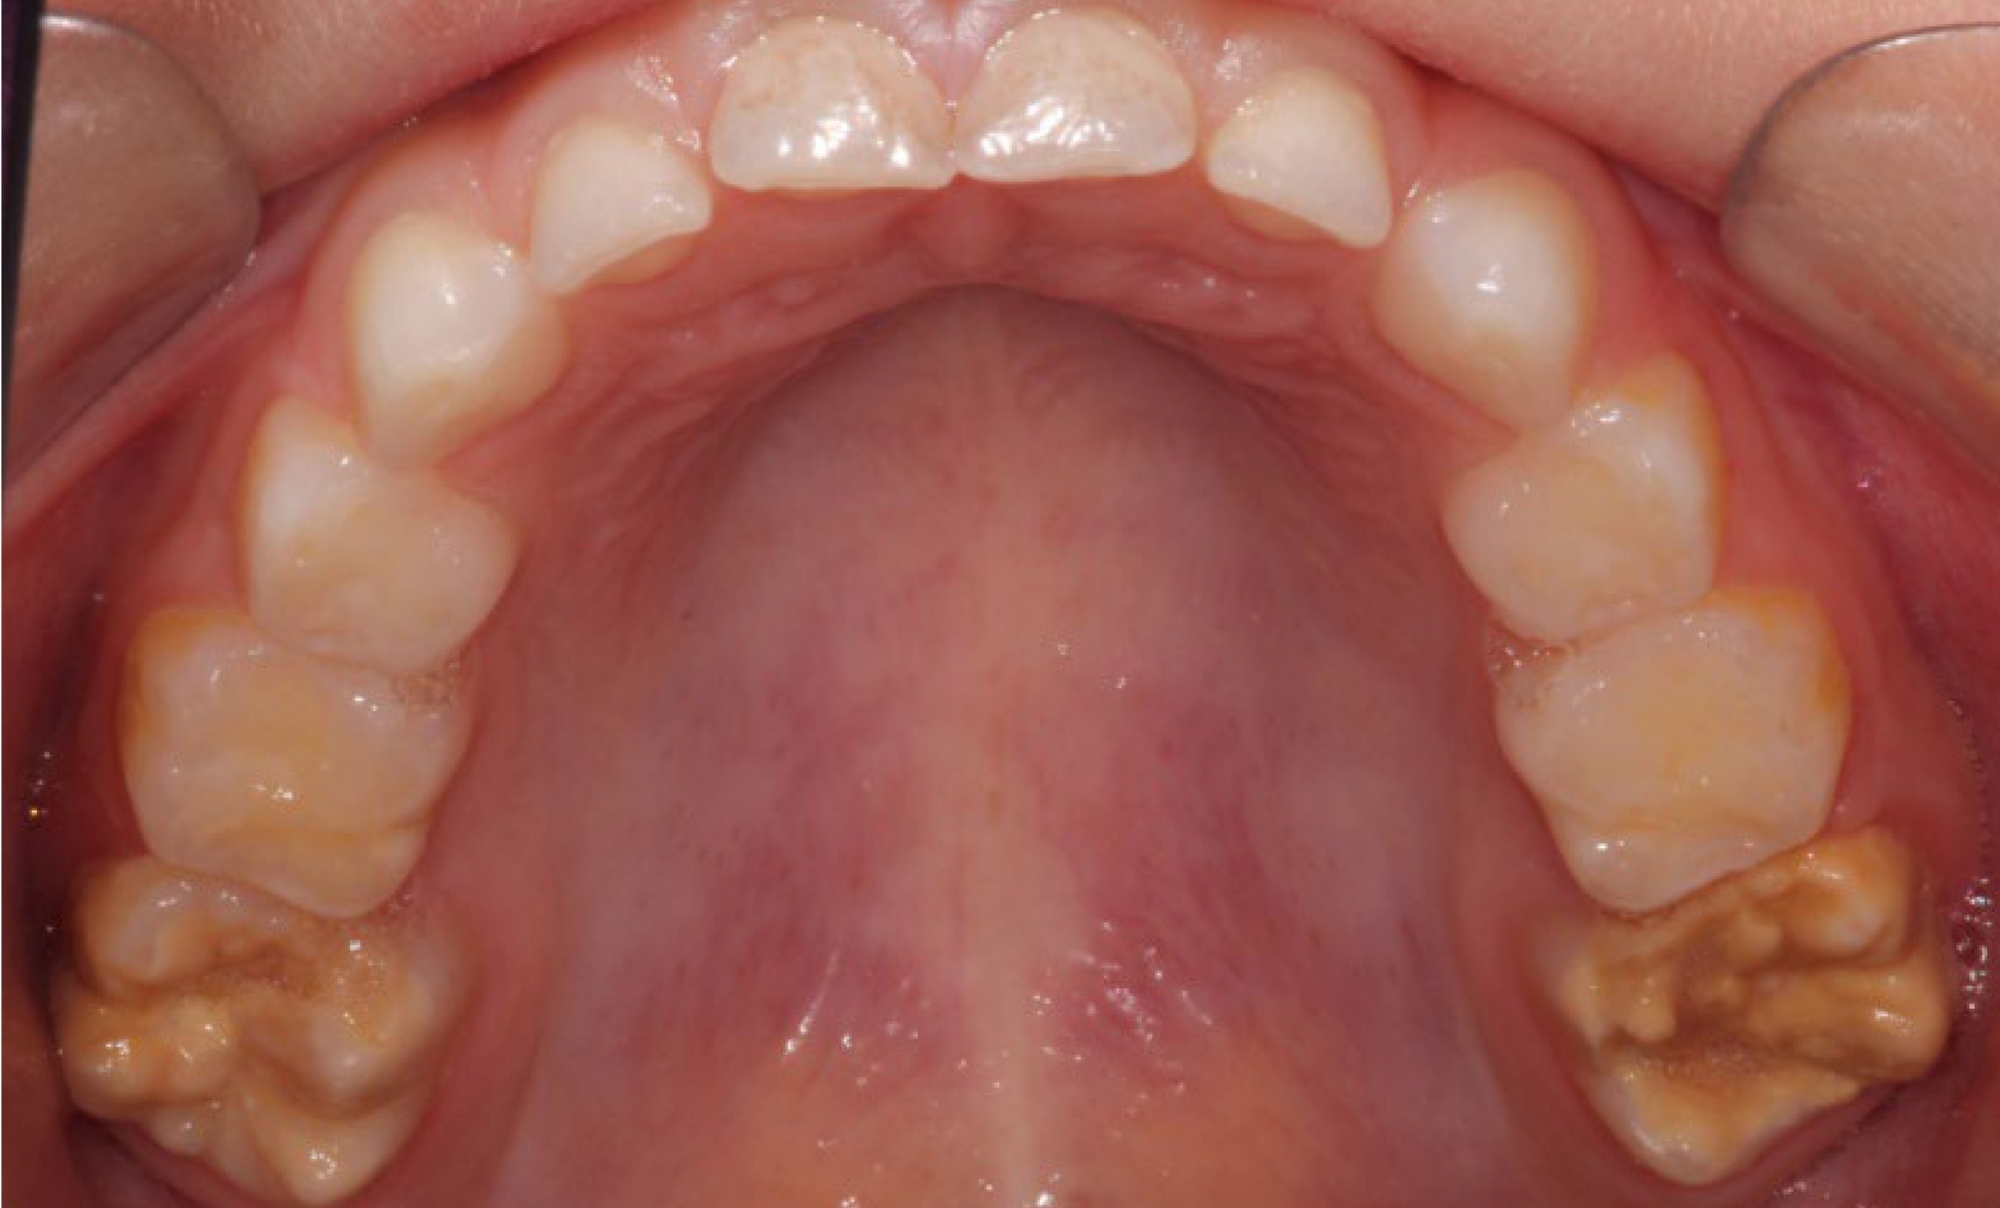

Kreidezähne haben oft gelblich-bräunliche Verfärbungen. © privat